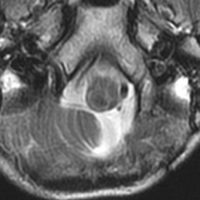

髄芽腫治療後17年目,放射線誘発血管腫からの脳幹部出血

1歳5ヶ月で左小脳半球の髄芽腫になり手術と化学療法して,3歳になってから脳脊髄照射をしました。脳脊髄18グレイ,局所48グレイが入っています。18歳の学生の時のMRIで,左小脳萎縮がありますが普通の生活ができています。

18歳の時に突然,左上下肢の痺れと脱力が生じました。延髄下端から脊髄に小さな出血があります。様子を見ていたら症状はよくなりました。

その後数日の間に,小さな出血を繰り返して,嚥下障害,しゃっくり,頭痛,四肢のしびれなどが出ました。手術をしないで経過を見ました。

7年後のMRIです。延髄脊髄移行部(おそらくC1)に出血痕が残っています。放射線誘発海綿状血管腫といわれるものの画像所見ですが,ほんとのところは静脈閉塞によるうっ血症状と鬱血性の出血といわれています。

症状はすべて良くなりました。今は学校を卒業して,元気に働いています。